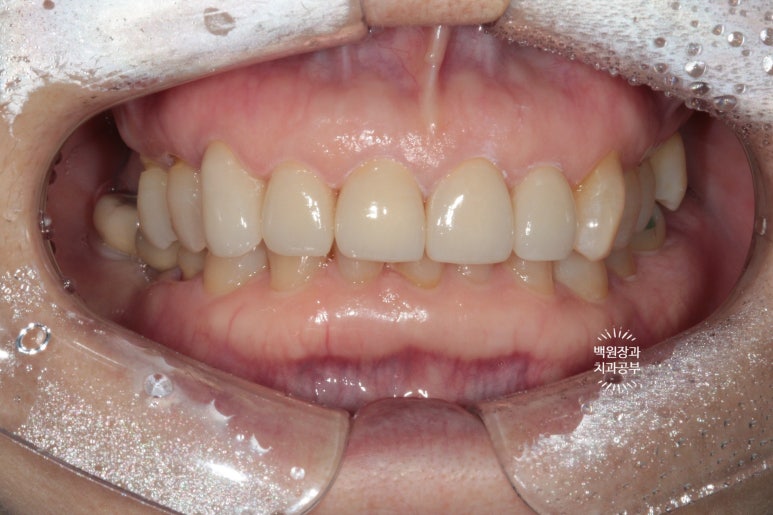

그랬지만, 이번에는 조금 어둡기도 하고, 송곳니가 길어보여서 만족스럽지 않다 말씀하신 환자분...

넵 그래도 수정 해드려야지요.

이렇게해서 두 번 수정한 앞니 지르코니아 크라운입니다.

처음에 비해 훨씬 가지런해지고 여성스러운 모양을 가진 치아로 완성되었네요!

어두운 배경을 깔고 촬영해보면 더더욱이 예뻐보이는 지르코니아 크라운입니다.